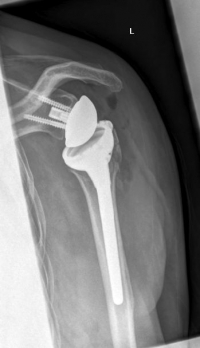

Bilder: Hier wurde ein subkapitaler Oberarmbruch mittels Anatomischer Prothese versorgt. Hierzu wurde der Oberarmkopf vollständig entfernt und durch die Prothese ersetzt. Diese ist im Oberarmschaft durch den Prothesenschaft verankert.

Bilder: Hier wurde ein Oberarmbruch mittels Inverser Schulterprothese bei mehrfragmentärerm Bruch mit Beteiligung der Gelenkfläche versorgt. Hierzu wurde der gebrochene Oberarmkopf entfernt und durch die (Endo-)Prothese ersetzt. Diese ist im Oberarmknochen durch den Prothesenschaft und im ehemaligen Gelenkpfannenbereich mit der sog. Glenosphäre mit Schrauben verankert. Anatomisch bewegt sich der runde Oberarmkopf in einer schalenförmigen Pfanne an der Schulter. Bei der Inversen Prothese werden Kopf und Pfanne miteinander getauscht (vgl. Bild Anatomische Prothese) , wodurch eine verbesserte Funktion bei bereits vorbestehenden Sehnenschäden der Rotatorenmanschette erreicht werden kann.